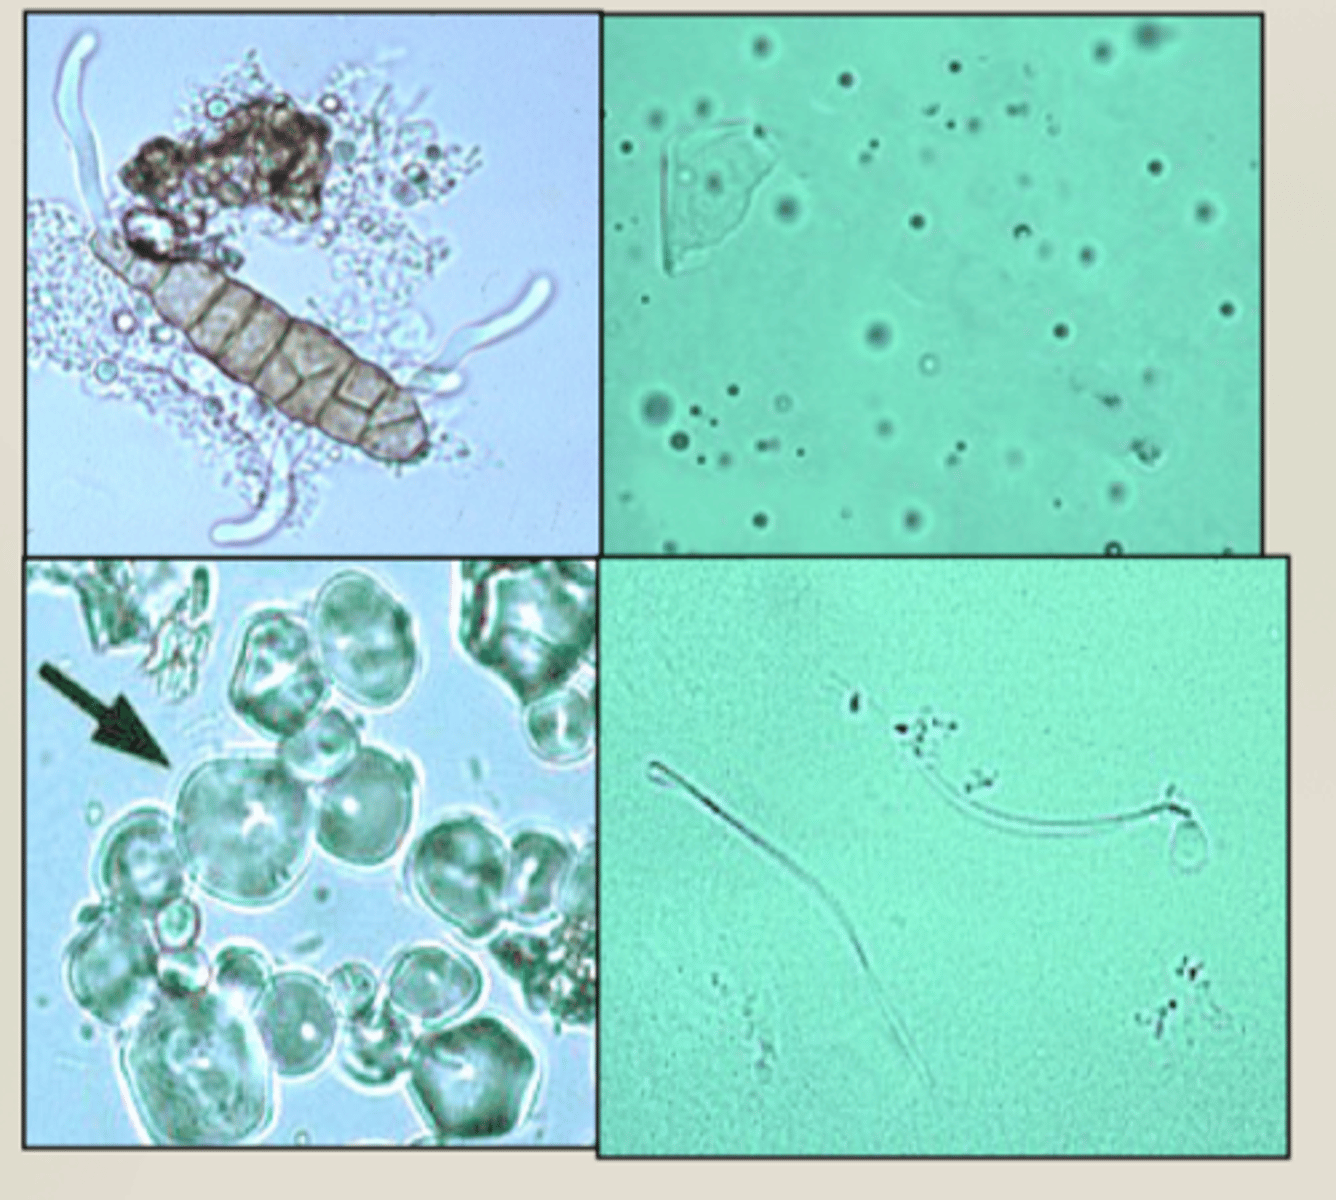

capillaria

urine

bi-polar plugs

sperm

urine

fungal spores

urine

upper left pic b/c I'm lazy

microfilaria

urine